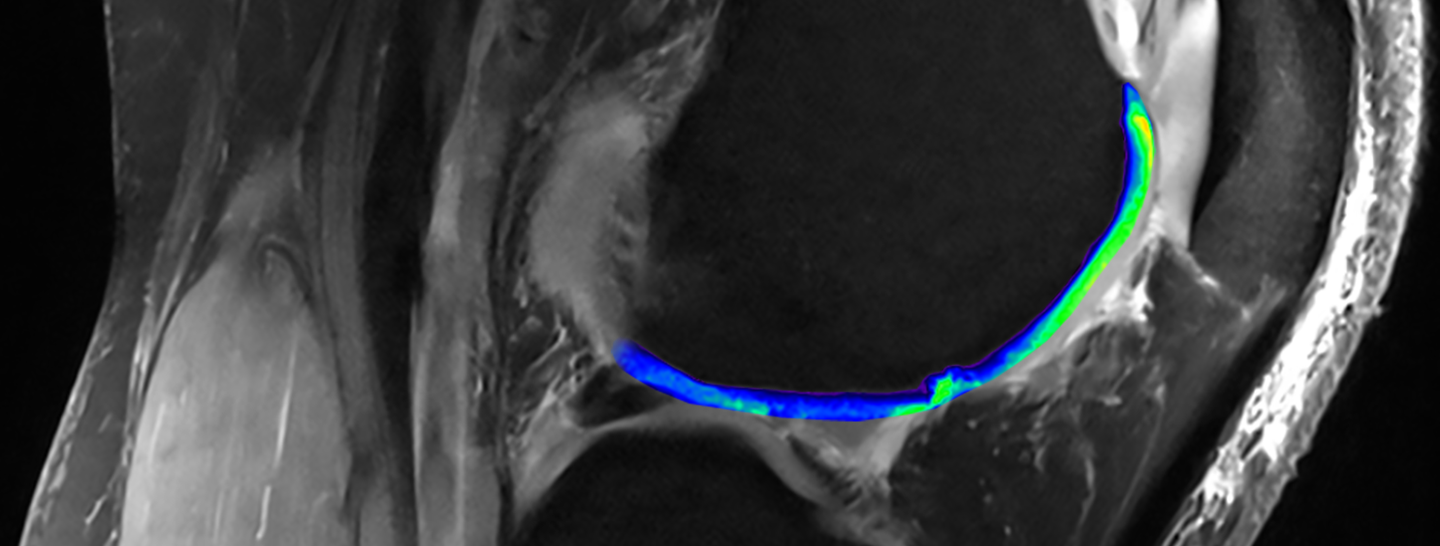

MRT-Bild

Das traditionelle MRT verwendet magnetische Impulse, um ein Signal von Wassermolekülen im Körper zu induzieren. Diese Technologie hebt den Knorpel (blau/hellgrün) visuell vom Knochen ab. Ein fortgeschrittenes MRT hat zwar den gleichen Ansatz, wendet ihn aber auf Natrium anstelle von Wassermolekülen an. Sie macht Proteoglykane (hellgrün), den besonderen Bestandteil eines hochwertigen Knorpels, sichtbar. Regionen ohne dieses Natriumsignal deuten auf einen defekten Knorpel hin. Bilder mit freundlicher Genehmigung von Siegfried Trattnig (modifiziert von Fidelis Onwubueke)

Zusätzlich zum Einsatz eines leistungsstarken MRT-Gerätes hat Trattnig Techniken entwickelt, die das Spektrum der Materialien erweitern, die MRT-Geräte erfassen können. So kann die Technologie beispielsweise den Proteoglykanspiegel, den besonderen Bestandteil eines hochwertigen Knorpels, eruieren.

Diese MRT-Aufnahmen zeigen auch Spalten im Knorpel (oben in dunklerem Blau), die auf eine Schädigung hinweisen. NIBR Forscher untersuchen, wie sie diese Lücken mit hochwertigem Knorpel im Zuge experimenteller Regenerations-Medizin schliessen können. Durch den Einsatz fortschrittlicher MRT in ihren klinischen Studien könnten sie einen Weg gefunden haben, die Qualität regenerierten Knorpels messen können – und all das ohne die Patienten einer schmerzhaften Biopsien auszusetzen.